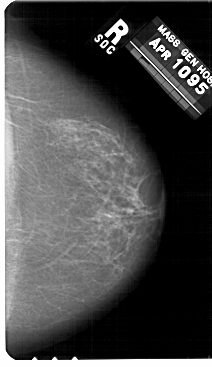

A_1479_1.RIGHT_CC

RIGHT_CC LINES 5491 PIXELS_PER_LINE 3166 BITS_PER_PIXEL 12 RESOLUTION 43.5 NON_OVERLAY